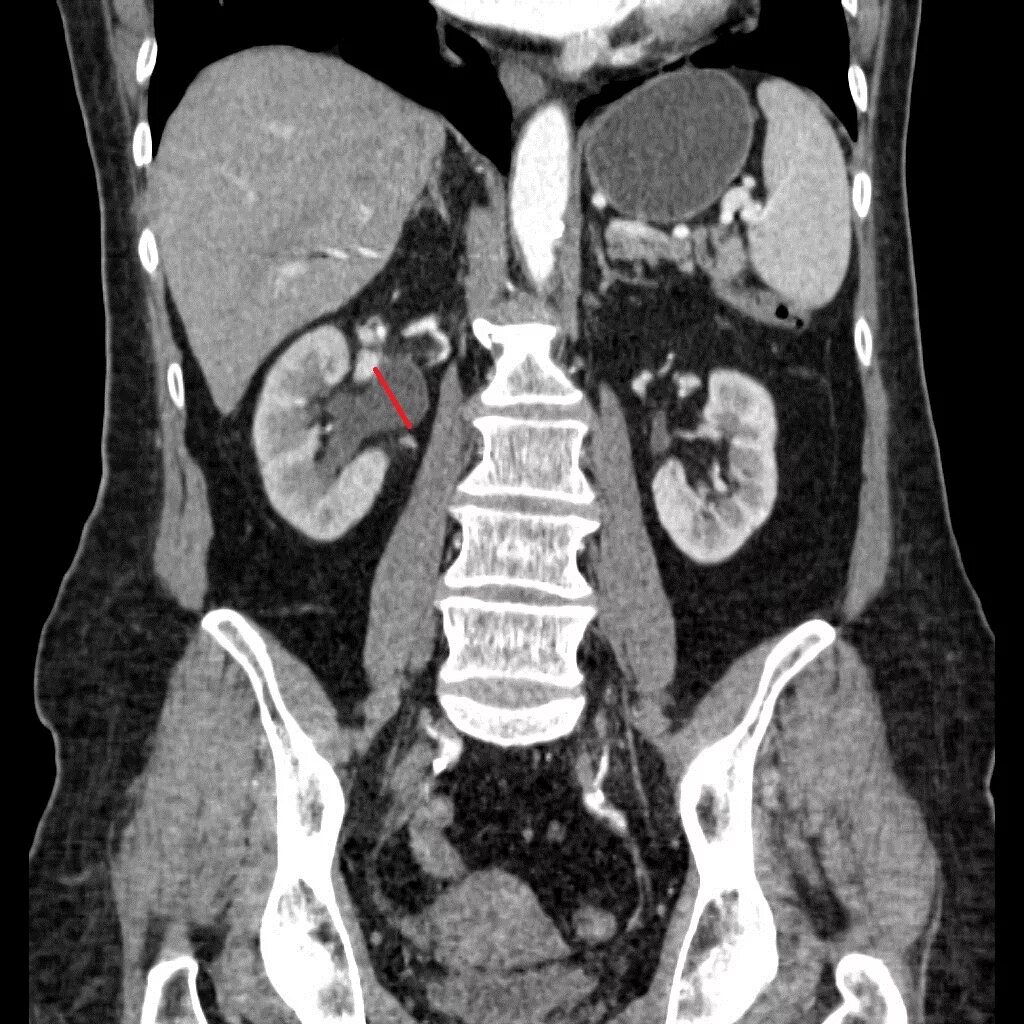

Как выглядит кт с контрастом